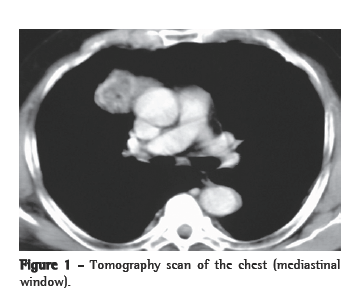

A 66-year-old male patient, born in the city of São Luiz (in the state of Maranhão) and a resident of the city of São Paulo (in the state of São Paulo), was admitted to the outpatient clinic presenting good general health status. The patient, who had no complaints, also had no history of morbidity or smoking. Radiological imaging, performed at another facility ten years prior, had revealed an anterior mediastinal tumor measuring approximately 4 cm in diameter. Therefore, we performed another round of chest X-rays and computed tomography scans of the chest. The new images revealed a tumor (3.0 × 4.0 cm) with spiculated margins, located in the right anterior mediastinum, with the same characteristics found on the scans performed previously (Figure 1). Laboratory test results and pulmonary function test results were normal. Tumors markers were normal. The syndromic diagnosis of anterior mediastinal tumor was confirmed, and surgical treatment was indicated.